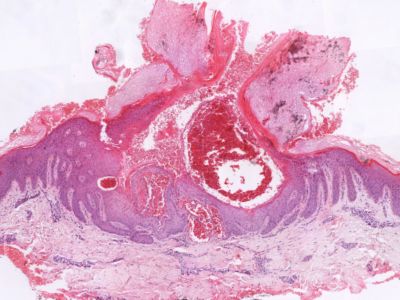

PA:

Direct onder de epidermis worden groepen van verwijde capillairen gezien. Naast hyperkeratose toont de epidermis acanthose en papillomatose. De verlengde retelijsten kunnen de capillairen geheel of gedeeltelijk omsluiten, zodat de verwijde capillairen intra-epidermaal lijken te liggen; ze zijn gevuld met bloed. Soms treedt thrombus vorming op.

Histologie angiokeratoma Histologie angiokeratoma

ingescande coupe (zoom) ingescande coupe (zoom)